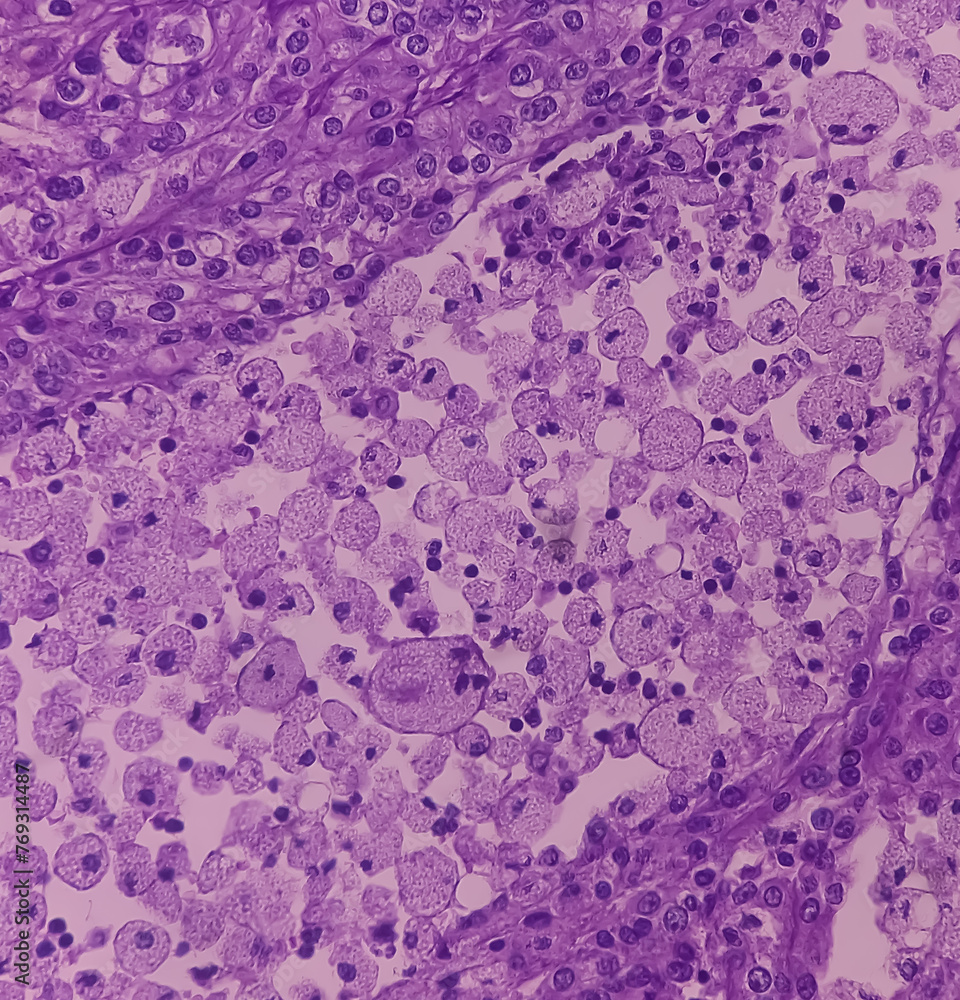

Il microscopio ottico sono visibili cellule tumorali che si dispongono formando cordoni, papille, tubuli o nidi. Possono esservi cellule atipiche, poligonali e di grandi dimensioni. Dal momento che queste cellule accumulano glicogeno e lipidi, il loro citoplasma appare più "chiaro", rivestito da lipidi, ed il nucleo rimane "contratto" nel mezzo delle cellule. La membrana cellulare è evidente. Alcune cellule possono essere più piccole, con citoplasma eosinofilo, che rassomiglia a quello delle cellule tubulari normali. Lo stroma che circonda le cellule si riduce, ma rimane ben vascolarizzato. Il tumore cresce tramite un ampio fronte, che comprime il parenchima circostante, dando luogo ad una pseudocapsula. [1]